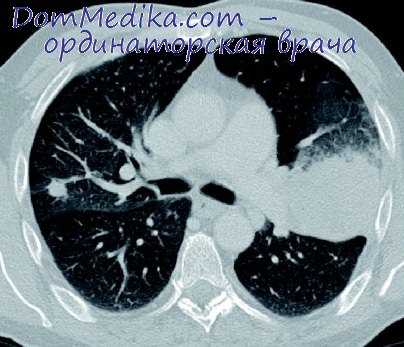

Лобэктомия - это частичное удаление легкого. Легкие - это два крупных органа, расположенных в грудной полости. Работа легких заключается в обеспечении движения и фильтрации кислорода и в обогащении кислородом крови. Кроме того, легкие защищают организм от дыма и других загрязняющих веществ, бактерий и вирусов. Они захватывают и частично уничтожают вредные вещества и микробов в слизи, которую сами же и вырабатывают. После этого слизь выводится из организма через кашель и/или глотание.

Каждое легкое состоит из нескольких долей: левое - из двух, правое - из трех. Правое легкое крупнее левого.